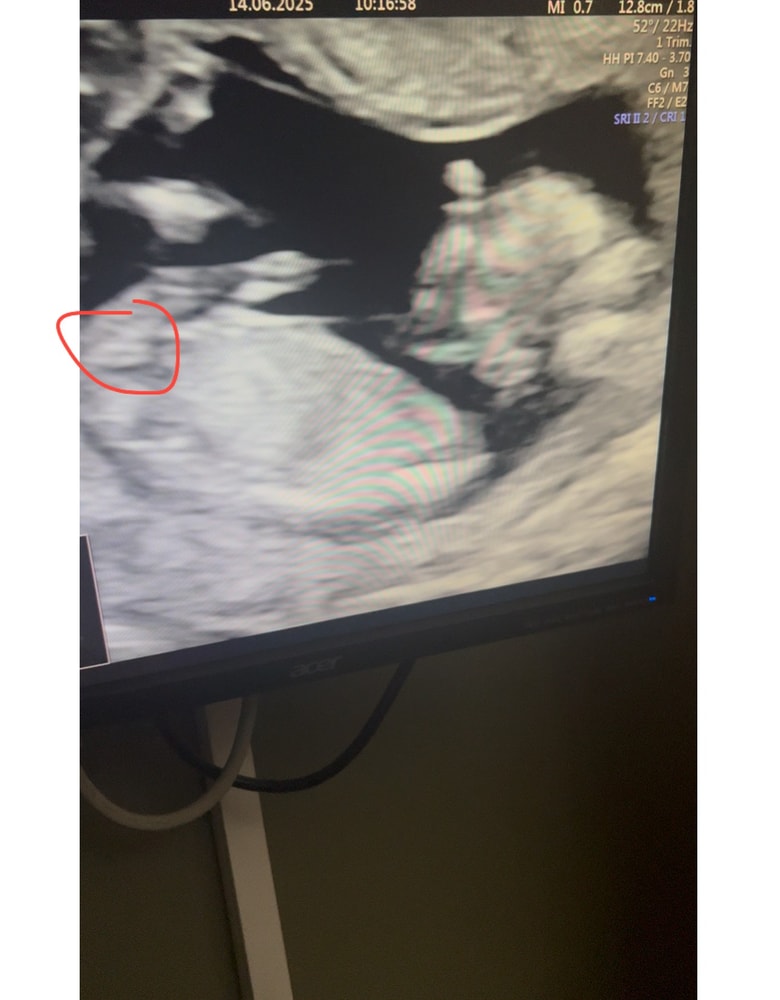

Гадание на пол ребёнка

1-ый триместр беременностиКак думаете? Давайте погадаем) просто ради интереса

Влада, да тут видно кофейное зернышко на всех фото 😄 ну и половой бугорок параллелен позвоночнику

Светлана, сегодня сдала кровь на определение Пола, ждем результаты и будем делать гендер пати🤗 врач предположил мальчика😁 Хотя срок уже 13,4 был на тот момент, я думаю у мальчика было бы все видно лучше намного аххаха